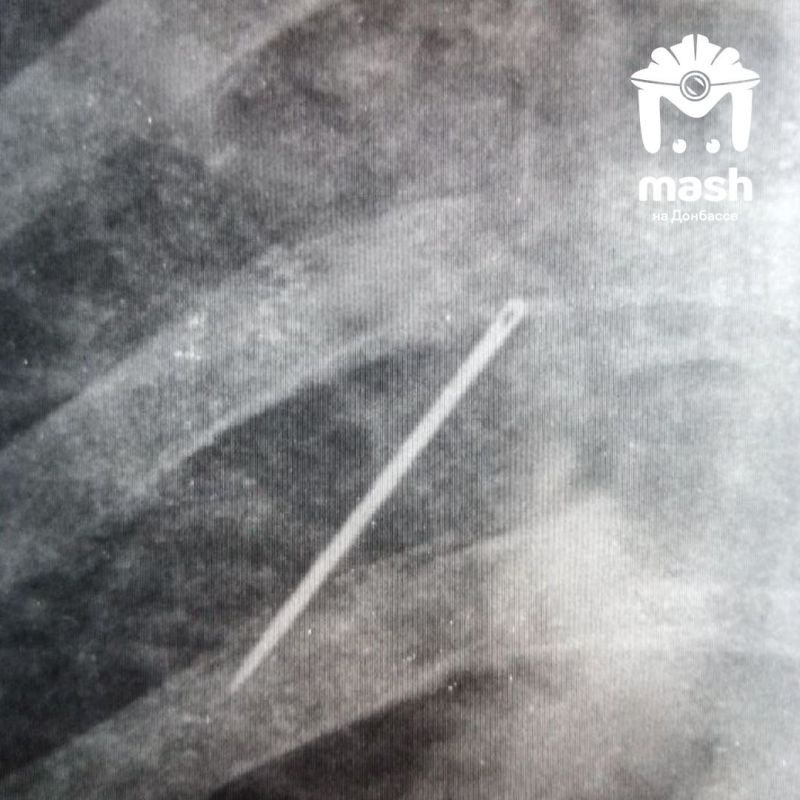

Пленный украинский военный со швейной иглой в лёгких попал к нашим полевым хирургам в Запорожской области.

Изначально его забрали с осколочным ранением. Во время осмотра медики сделали рентген и увидели иглу — начали задавать вопросы. Тот сказал, что сам воткнул ее — надеялся попасть домой, как трехсотый. Мол, его насильно мобилизовали, а он воевать не хочет. Но его командованию было плевать — все равно отправили на штурм. Через несколько недель его забрали российские бойцы.